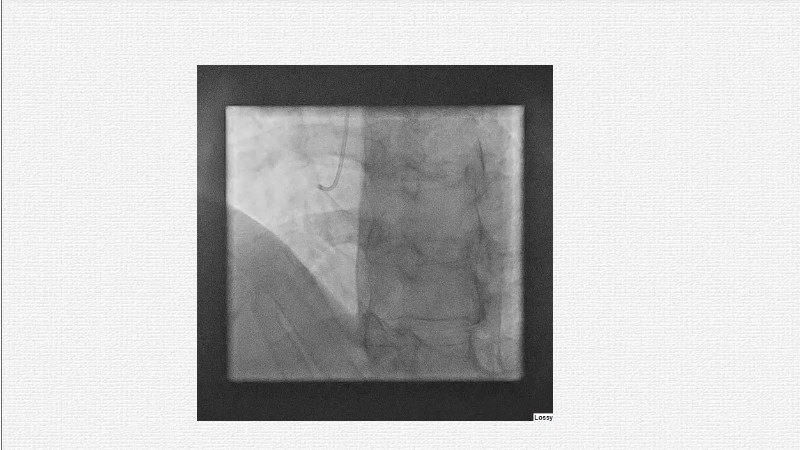

This EuroPCR 2025 session challenges the conventional approach to bifurcation PCI and dissection management. Learn why drug-coated balloons (DCB) may offer better long-term outcomes in cases where stents fall short, how DCBs can simplify bifurcation strategies, and why it’s time to rethink which dissections really need stenting. Through data, case examples, and clear decision-making insights, you'll gain the confidence to broaden your DCB practice where it truly matters.

- To analyse clinical data and use case of drug-coated balloons in bifurcation PCI